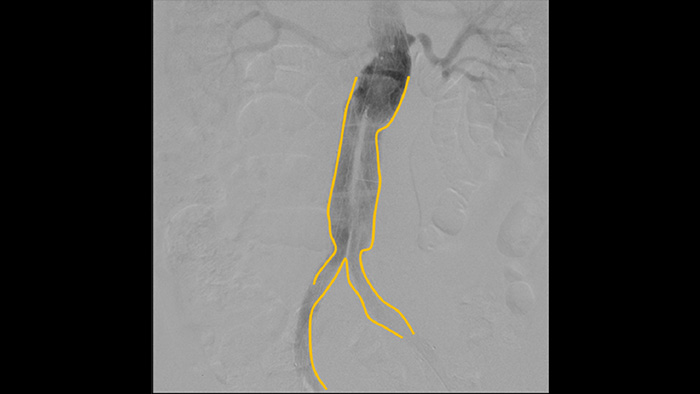

A angiografia de subtração digital (DSA) é utilizada em procedimentos vasculares de intervenção para visualizar claramente os vasos sanguíneos através da remoção de estruturas que possam obscurecer a visibilidade dos vasos. A fluoroscopia de mapeamento sobrepõe uma imagem de contraste subtraída adquirida anteriormente na fluoroscopia em tempo real, permitindo-lhe monitorizar um dispositivo sem reinjetar contraste.

Ferramenta de contorno para marcação de bifurcações ou ramos laterais

Utilize a ferramenta Contorno para marcar facilmente uma bifurcação ou ramos laterais, simplesmente desenhando no monitor da estação de visualização móvel com o dedo ou com um rato ligado externamente.